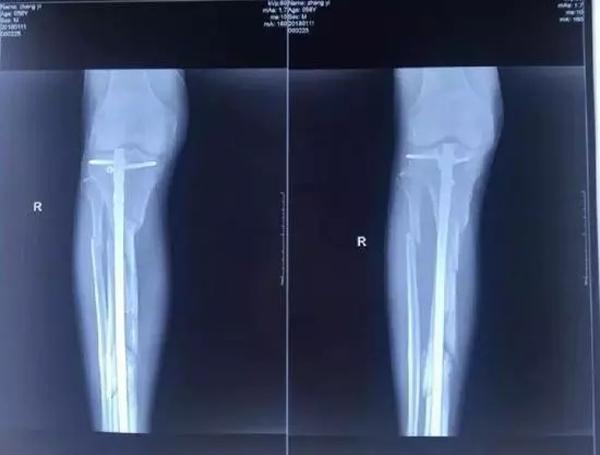

他興辦的廊坊市城南骨科醫(yī)院發(fā)展得越來越好,引起了原本是小股東的楊玉忠對醫(yī)院的覬覦。股東如果想要擴大股權(quán),有許多正常的途徑,用合理合法的方式完全可以實現(xiàn)。但楊玉忠卻采取了最直接卻也最暴力的方式,不斷用欺騙、騷擾、干預(yù)人事等方式排擠張毅,使他在專心看病的同時,疲于應(yīng)付,心理壓力極大,甚至在2017年10月18日,張毅被四名駕駛無牌豪華越野車的黑衣人打斷腿骨。即使是如此,當?shù)睾趷簞萘σ廊粵]有放過張毅,不僅舊醫(yī)院被掏空占據(jù),新醫(yī)院也無法開張,200多醫(yī)護人員面臨衣食無著的困境。雖多方求助,對方依然逍遙法外,最終逼死了張毅。

資料圖